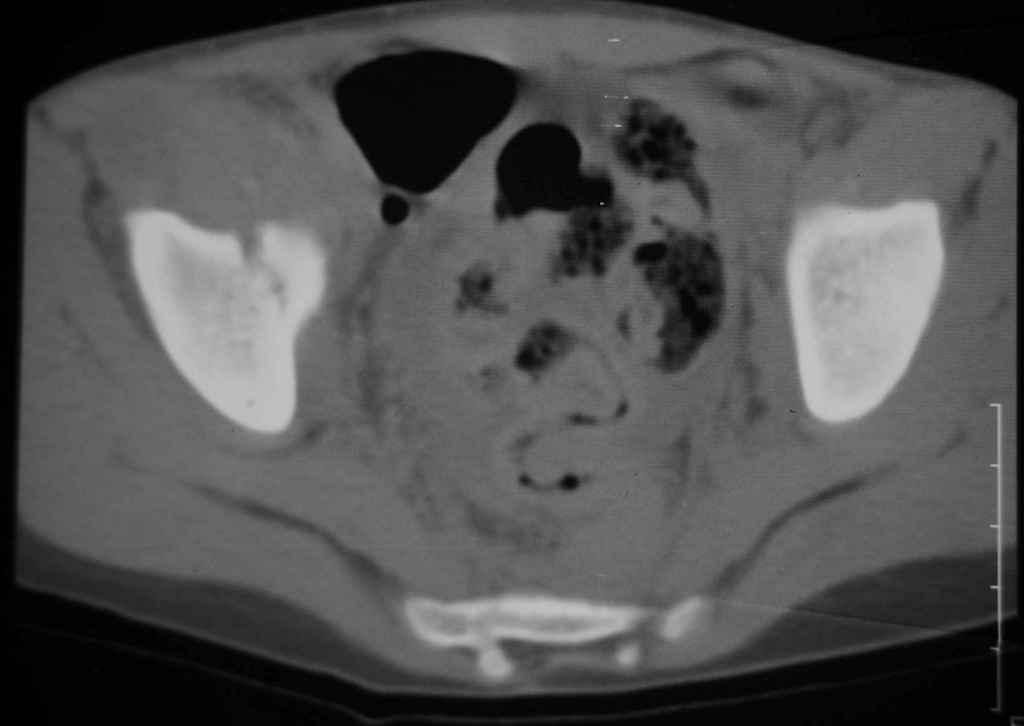

Перелом вертлужной впадины

Уважаемые коллеги, помогите определиться с тактикой лечения.Ребёнок 7 лет, травма 11.09.08, поступил с травматическим вывихом бедренной кости.

Вывих вправлен, конечность фиксирована на скелетном вытяжении. Что делать с переломом подвздошной кости? Лечить консерватино или оперировать?